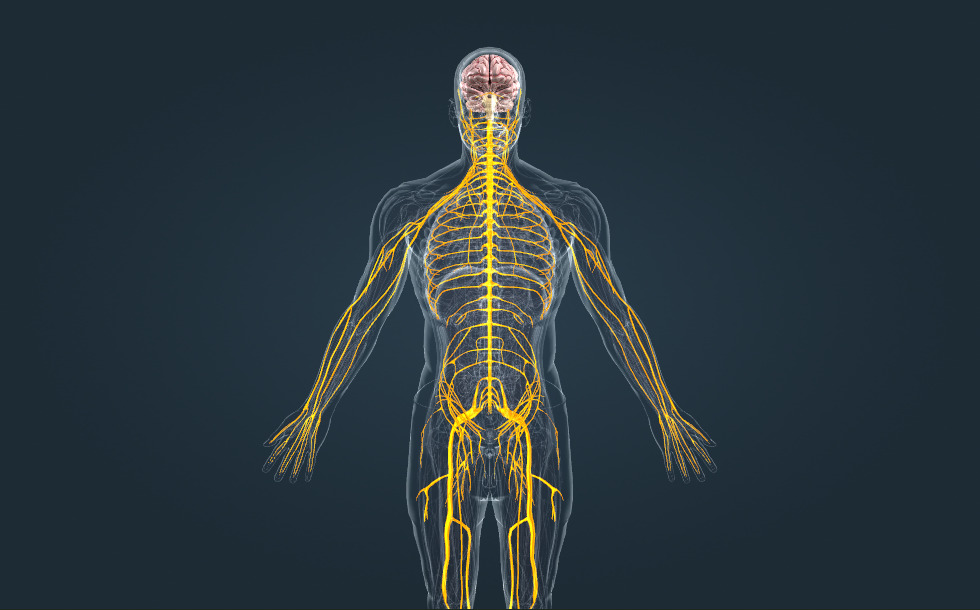

Zenuwstelsel

- hersenen - Bevindt zich in de schedel.

- ruggengraat - Bevindt zich in de wervelkolom.

- zenuwen - Ze bestaan uit zenuwvezels die het centrale zenuwstelsel verbinden met de verschillende organen.

Het zenuwstelsel is samen met het hormonaal stelsel verantwoordelijk voor de gecoördineerde, gereguleerde werking van het lichaam. Het centrale zenuwstelsel bestaat uit de hersenen en het ruggenmerg, terwijl het perifere zenuwstelsel bestaat uit zenuwen, welke informatie tussen het centrale zenuwstelsel en de organen overdragen via elektrische signalen. Er zijn 12 paar hersenzenuwen, die rechtstreeks vertakken uit de hersenen en 31 paar spinale zenuwen die vertakken uit segmenten van het ruggenmerg.

Het zenuwstelsel is samen met het hormonaal stelsel verantwoordelijk voor de gecoördineerde, gereguleerde werking van het lichaam. Het centrale zenuwstelsel bestaat uit de hersenen en het ruggenmerg, terwijl het perifere zenuwstelsel bestaat uit zenuwen, welke informatie tussen het centrale zenuwstelsel en de organen overdragen via elektrische signalen. Er zijn 12 paar hersenzenuwen, die rechtstreeks vertakken uit de hersenen en 31 paar spinale zenuwen die vertakken uit segmenten van het ruggenmerg.